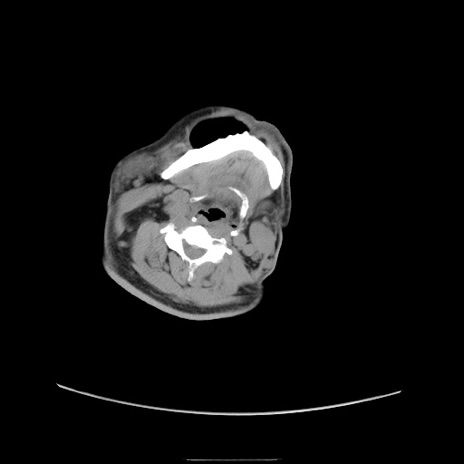

冠状断像

【症例】50歳代男性

【主訴】腹痛

【現病歴】AVMからの被殻出血のため回復期リハ病棟入院中。 本日午後3時頃急に下腹部痛が出現した。

【既往歴】AVM、被殻出血、虫垂炎、高血圧

【身体所見】意識晴明、左半身不全麻痺、会話の理解は良好、36.5°C、腹部:膨隆、全体に板状硬、下腹部正中に圧痛点あり、反跳痛-、筋性防御不明、右下腹部にope scar

【データ】WBC 9400、CRP 0.06